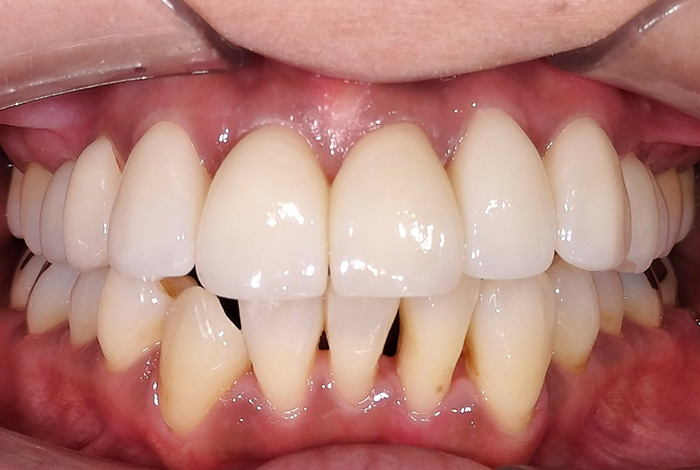

Before

After

インビザラインによる全体矯正後に補綴治療を行い、咬合と審美性を総合的に改善した症例です。

まずマウスピース型矯正装置(インビザライン)により歯列および咬合関係を整え、その後、必要部位にジルコニア補綴を行いました。

矯正のみ・補綴のみではなく、両治療を組み合わせることで機能性と審美性の両立を目指した包括的治療です。

奥歯の噛み合わせと前歯の歯並びを同時に改善した症例(インビザライン+ジルコニア)

【治療前の状態】

患者様は、奥歯でしっかり噛めないことと、前歯の歯並びの乱れを気にされ来院されました。診査の結果、前歯部の叢生(歯並びの乱れ)と、臼歯部の離開咬合(奥歯がしっかり噛み合っていない状態)が認められました。また、臼歯部には古い金属修復物が装着されており、機能面だけでなく審美面においても改善が必要な状態でした。

【治療後】

前歯の歯並びが整い、見た目の改善が認められました。また、奥歯でしっかり噛める状態となり、咬合機能の回復が得られています。

【治療のポイント】

本症例では、歯並びの改善だけでなく、噛み合わせの回復と審美性の向上を同時に行っています。当院は一般歯科と矯正治療の両方に対応しているため、矯正治療後に別の医療機関で補綴治療を行う必要がなく、一貫した治療計画のもとで治療を完結することが可能です。また、奥歯の噛み合わせを矯正治療のみで改善する場合、治療期間が長くなることがありますが、本症例では補綴治療(アンレー)を併用することで、比較的短期間で咬合の改善を行いました。さらに、古い金属修復物をジルコニアに置き換えることで、見た目の改善と機能性の両立を図っています。